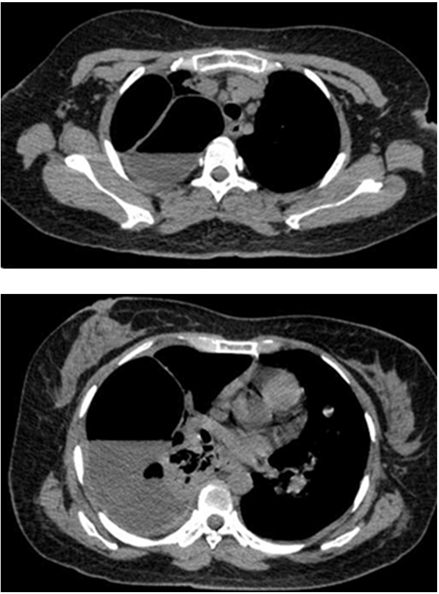

A 35-year-old Indonesian mongoloid female patient presented with a painful lump in her left leg. She had history of lump in her left leg since seven years prior to admission. Initially, the lump was only 1 cm in diameter. There was no history of trauma. The patient was initially treated by general surgeon, and had undergone excision of the lump. After the surgery, recurrence occurred and the lump developed gradually. Within seven years, the patient did not routinely visit hospital to have the condition of the lump checked. One week prior to admission, the patient complained about difficulty in breathing. She came to a primary hospital and was found to have a pleural effusion in her right lung and chest tube was inserted. She was then referred to our hospital. On the physical examination, a 10x10x5 cm hard tender mass was found in the left lower leg (Figure 1). Range of movement (ROM) in the left knee joint was full, but in the ankle joint, the ROM was limited. Laboratory results including tumor marker were unremarkable. Plain radiograph of the left leg showed lytic lesion in diaphysis and metaphysis of the left tibia with osteodestruction of tibia and extension to the surrounding soft tissue (Figure 2). A chest radiograph was performed (Figure 3) which showed bullae in the superior lobe of the right lung, pneumothorax, fibroatelectasis in the middle lobe of the right lung, and right pleural effusion. A chest MSCT showed hydropneumothorax and multiple bullae of the right lung and solitary nodule in the left lung suspected to be a distant metastasis from the primary tumor site (Figure 4). The patient was assessed with hydropneumothorax of the right lung caused by possible malignancy. A fine needle aspiration biopsy (FNAB) of the lesion in the left leg then performed with the result of clustered tumor cells within a group, with small cells with atypia, small amount of cytoplasm, spindle nucleus with hyperchromasia with background of lymphocyte and erythrocyte (Figure 5). A clinicopathological conference was then arranged with a recommendation of transfemoral amputation. A transfemoral amputation was then performed and the histopathological result showed a pattern of epithelial tumor with solid arrangement and infiltration to surrounding tissue, including to the upper dermis. The observation of the cells showed small to moderate cell sizes, small amount of cytoplasm, round to spindle nucleus with small amount of mitosis. The conclusion of the histopathological examination was islands of epithelial cells in a densely-populated stroma of spindle cells suggesting adamantinoma (Figure 6). The positive cytokeratin was found in the immunohistochemistry on the tumor cells and it was also relevant with the diagnosis of adamantinoma (Figure 7). | ||||||

The symptoms initially present with nonspecific characteristics and its variety of the symptoms is related to location and extent of the disease. Pain is the most common clinical manifestation reported. It was in accordance to this case where the patient was presented with painful lump on her left lower leg. The onset of the clinical sign and symptom is insidious with slow and progressive characteristic. The patient usually tolerates symptoms for many years before seeking medical attention because of this characteristic of clinical manifestation as seen in this patient [5]. However, some of the patients present with swelling with or without pain as local swelling being the second most common symptom to appear. In addition, this case also showed that involvement of the anterior tibial surface can produce bowing of the tibia [6]. Based on radiographic assessment, adamantinoma is an osteolytic type with mono or multi-loculated lesions. In accordance to its benign characteristics, it is well circumscribed with septa and a peripheral condensation may appear. It is usually appear in the diaphysis or metaphysis of the anterior tibial. The lesion usually grows intracortical and it may spread longitudinally. However, it does not rule out the possibility of cortex destruction and marrow cavity invasion of the tumor [7]. The MSCT examination could reveal the characteristics of the lesion better than plain radiograph and can also detect another tumor site invisible on plain radiographs. The differential diagnosis based on plain radiograph examination including fibrous dysplasia and osteofibrous dysplasia [2]. . The patient in this case had tumor in her left leg which develops progressively after the first excision seven years ago. This might be due to inadequate attempts of removal where incomplete resection may result in higher recurrence rate up to 30% in the period of 85 months. Therefore, adamantinoma is suggested to be treated with wide surgical excision and reconstruction or amputation since its likelihood of healing is high subsequent to radical treatment [2] [3]. If early diagnosis is successfully made, wide local excision with a substantial margin of normal bone is still acceptable [8]. However, if there has been more than one recurrence or in large tumor with extension to the surrounding soft tissues, radical resection or amputation is advisable as shown in this patient where knee amputation was performed [9]. Adamantinoma is a low-grade malignant tumor of epithelial origin which metastasizes late. This tumor is insensitive to radiation and has capabilities of metastasis, especially to the lung. [8]. Metastases including in lung or lymph nodes are rare and can occur in 10–20% of patients. Pulmonary metastases are more common that regional nodal metastases from this tumor. It is not uncommon to develop distant metastases even up to 10 years after detection of the primary [3] [5]. This was in accordance with this case, where the main reason to seek medical management was due to difficulty in breathing and it was correlated with repeated local recurrences that might be due to inadequate primary excision of the tumor. However, it is difficult to evaluate its true metastatic potential due to several reasons such as long term follow-up, low number of the case, and slow growing nature of the tumor [5]. Several reports in literature have described metastasectomy for pulmonary lesions in both curative and palliative settings with good results. Mean survival of patients with metastatic disease is reported to be 12 years. There appears to be no definitive role for radiotherapy or chemotherapy [10]. Due to its excellent prognosis, it is crucial to diagnose this rare bone tumor in the early stage. It can be achieved by histologic examination, where this tumor can be distinguished easily. However, not only this tumor is rare, the heterogeneity of the tumor presentation may lead to confusion in some cases. On the histologic examination with inadequate sample taking, epithelial component may be seen only focally in the differentiated adamantinoma case, therefore in some cases, extensive sampling of the tumor is mandatory [11]. The challenge in making diagnosis and preparing proper management emphasizes that clinicopathological conference among orthopedic surgeon, pathologist, and radiologist was very important to ensure the patient get the best treatment available in musculoskeletal tumor cases. At the moment where the diagnosis is certain, resection with wide surgical margins or amputation can be applied to the patient.. | ||||||